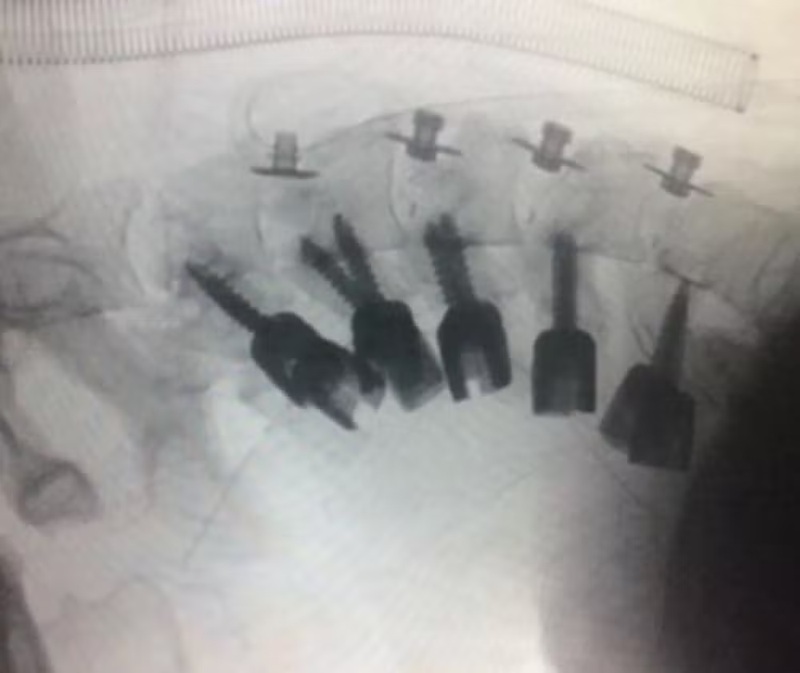

Os exames mostraram que a musculatura do paciente estava preservada, mas sua coluna estava gravemente deformada. Por isso, foi necessário fazer uma intervenção cirúrgica para ajudar a reverter o quadro, com a remoção do osso deformado e o uso de pinos e uma gaiola de bloqueio para sustentação da cabeça.